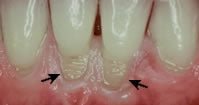

Many people are brushing their teeth too hard and using toothpaste that is extremely abrasive. Did you know that most 'whitening' toothpaste uses abrasion to make your teeth whiter?